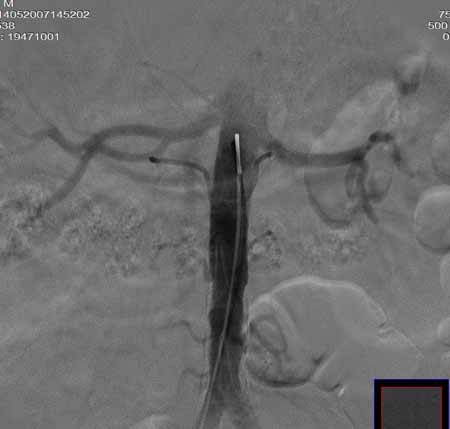

男,60岁。

腹主动脉、颈总动脉、颈内动脉狭窄支架置入术,最少放了三个支架吧,得十几万吧。

颈总动脉支架置入术。